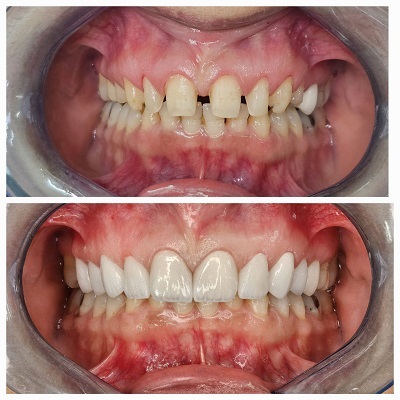

دکتر حامد رحیمی

دکتر حامد رحیمی متولد سال ۱۳۶۷ می باشند.ایشان در سال ۱۳۸۵ موفق به ورود به رشته دندانپزشکی دانشگاه علوم پزشکی تهران شدند و در سال ۱۳۹۱ فارغ التحصیل گردیدند.در سال ۱۳۹۴ پس از گذراندن طرح دوره دکتری عمومی در استان قم موفق به قبولی در رشته جراحی لثه و ایمپلنت دانشکاه علوم پزشکی تهران گردیدند.ایشان از سال ۱۳۹۷ و پس از کسب بورد تخصصی به عنوان عضو هیات علمی دانشگاه علوم پزشکی قم مشغول هستند.